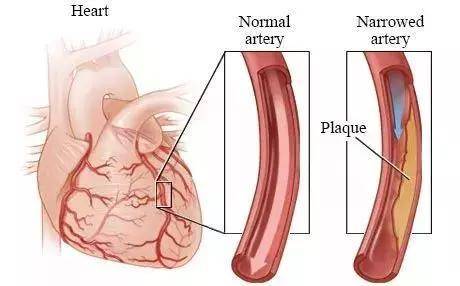

冠狀動脈狹窄

心臟支架手術,簡單來說就通過穿刺血管,讓導管順著血管一路前行。

在導管到達病灶後,再用特殊的傳送裝置將支架輸送到位。

其實相比需要開胸的心臟搭橋手術,很多情況下,支架手術有更強的普適性。

術後24小時能下床,3天即出院,這都是搭橋手術不可能達到的優勢。